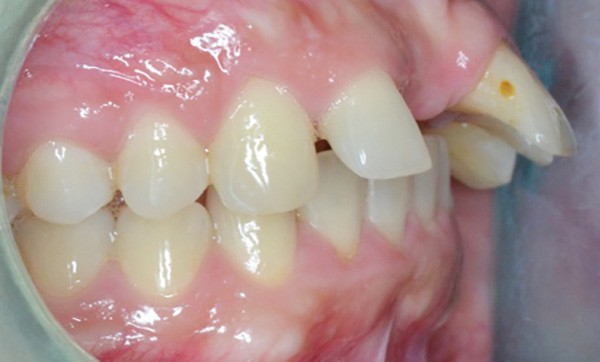

Charlotte présente donc une absence de 11, un surplomb et un recouvrement augmentés associés à une retromandibulie. La patiente a un profil convexe, hypodivergent avec une proalvéolie maxillaire et une classe II d’Angle. (fig. 1a à h). La radiographie panoramique confirme l’absence de 11 et la téléradiographique de profil, révèle une classe II squelettique (ANB : 6°, AoBo : 9 mm) par rétromandibulie ainsi qu’une proalvéolie maxillaire prononcée.

Il a été décidé de mettre en place un traitement ortho-chirurgical avec multi-attaches maxillaire et mandibulaire et avancée mandibulaire première (fig. 3a) [1]. Ce traitement est réalisé en technique d’arc droit avec des attaches vestibulaires informées en Roth en .022 x .028. Il durera quinze mois, pose d’implant comprise.

La patiente est appareillée une semaine avant la chirurgie d’avancée mandibulaire première sans mise en place de l’arc (Chirurgie réalisée par le Dr Laurentjoye). Dix jours après la chirurgie, les premiers arcs (.016 Niti) sont mis en place, avec l’utilisation de tractions intermaxillaires d’intercuspidation tendance classe II (fig. 3b). Après la réalisation du traitement et la mise en place d’une dent provisoire sur l’arc à la taille et la forme souhaitées…